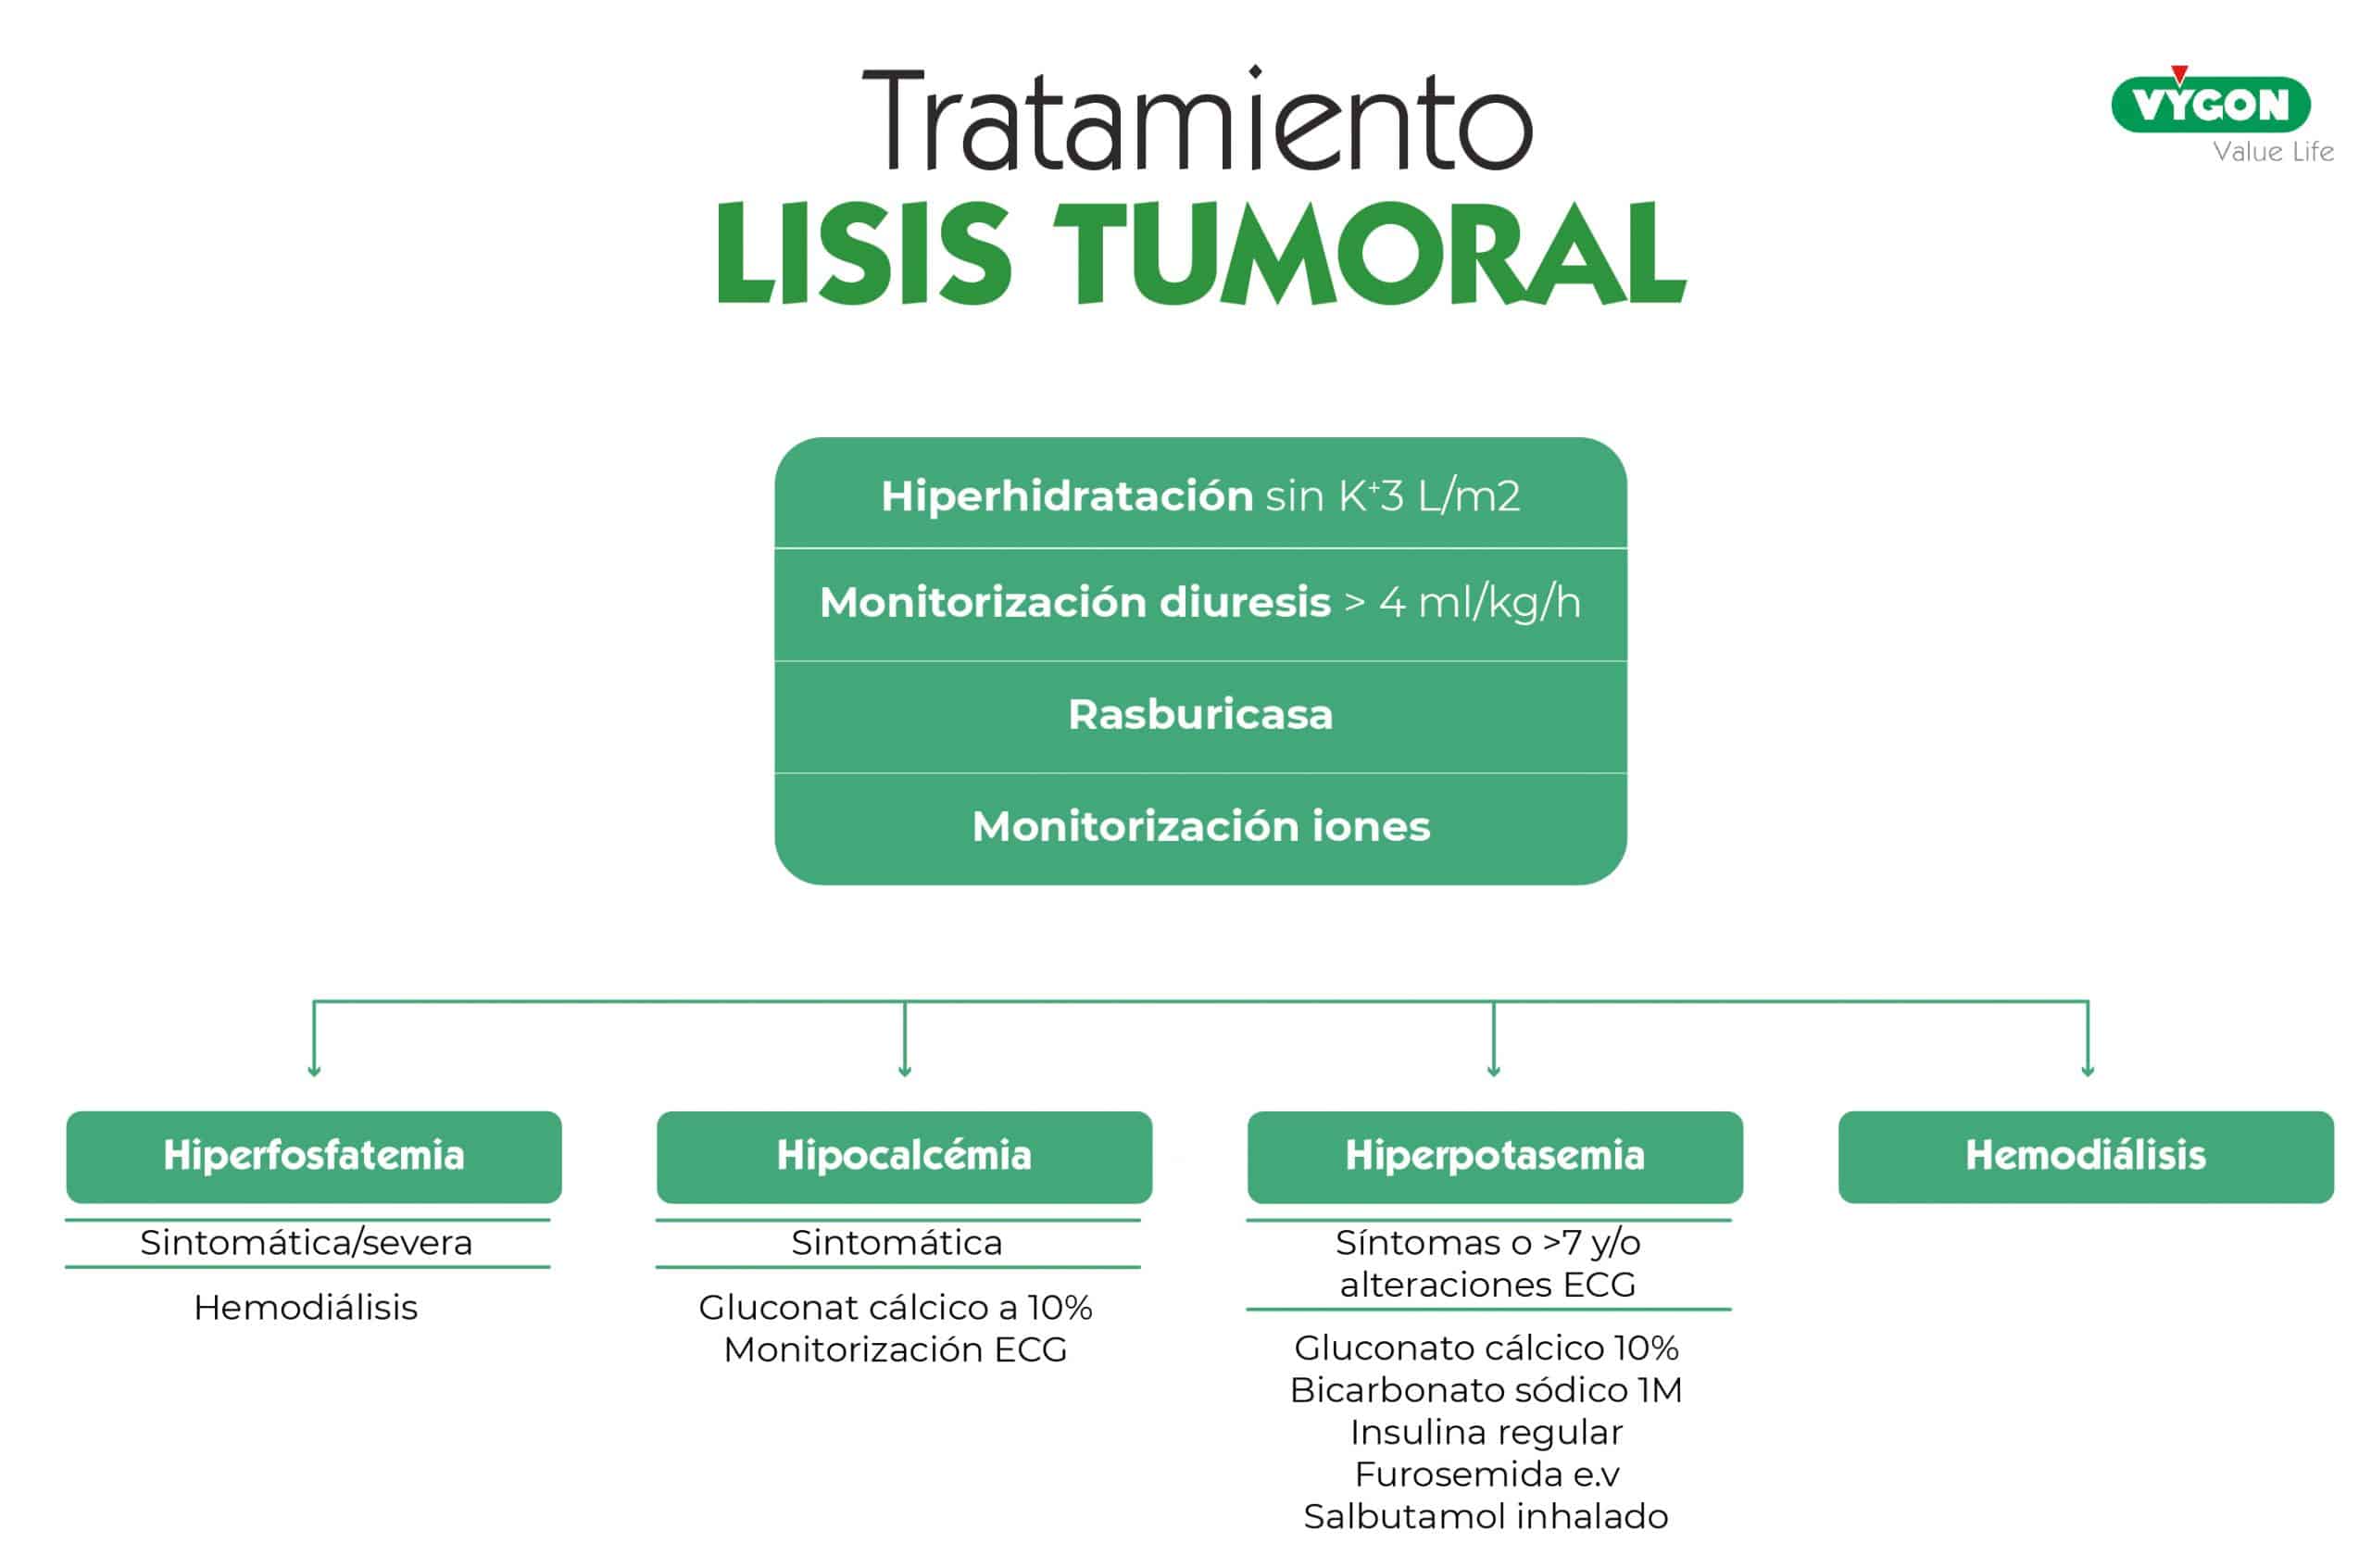

El tratamiento, que ya se había comenzado a administrar al paciente incluye:

- Hiperhidratación sin K+ 3 L/m2

- Monitorizacióń diuresis > 4 ml/kg/h

- Rasburicasa

- Monitorización iones

Se optimiza tratamiento médico de la hiperpotasemia con gluconato cálcico, insulina, bicarbonato, salbutamol y furosemida, con lo que se consigue un descenso en la cifra de potasio, que se mantiene entre 5,5-6,5mmol/l.